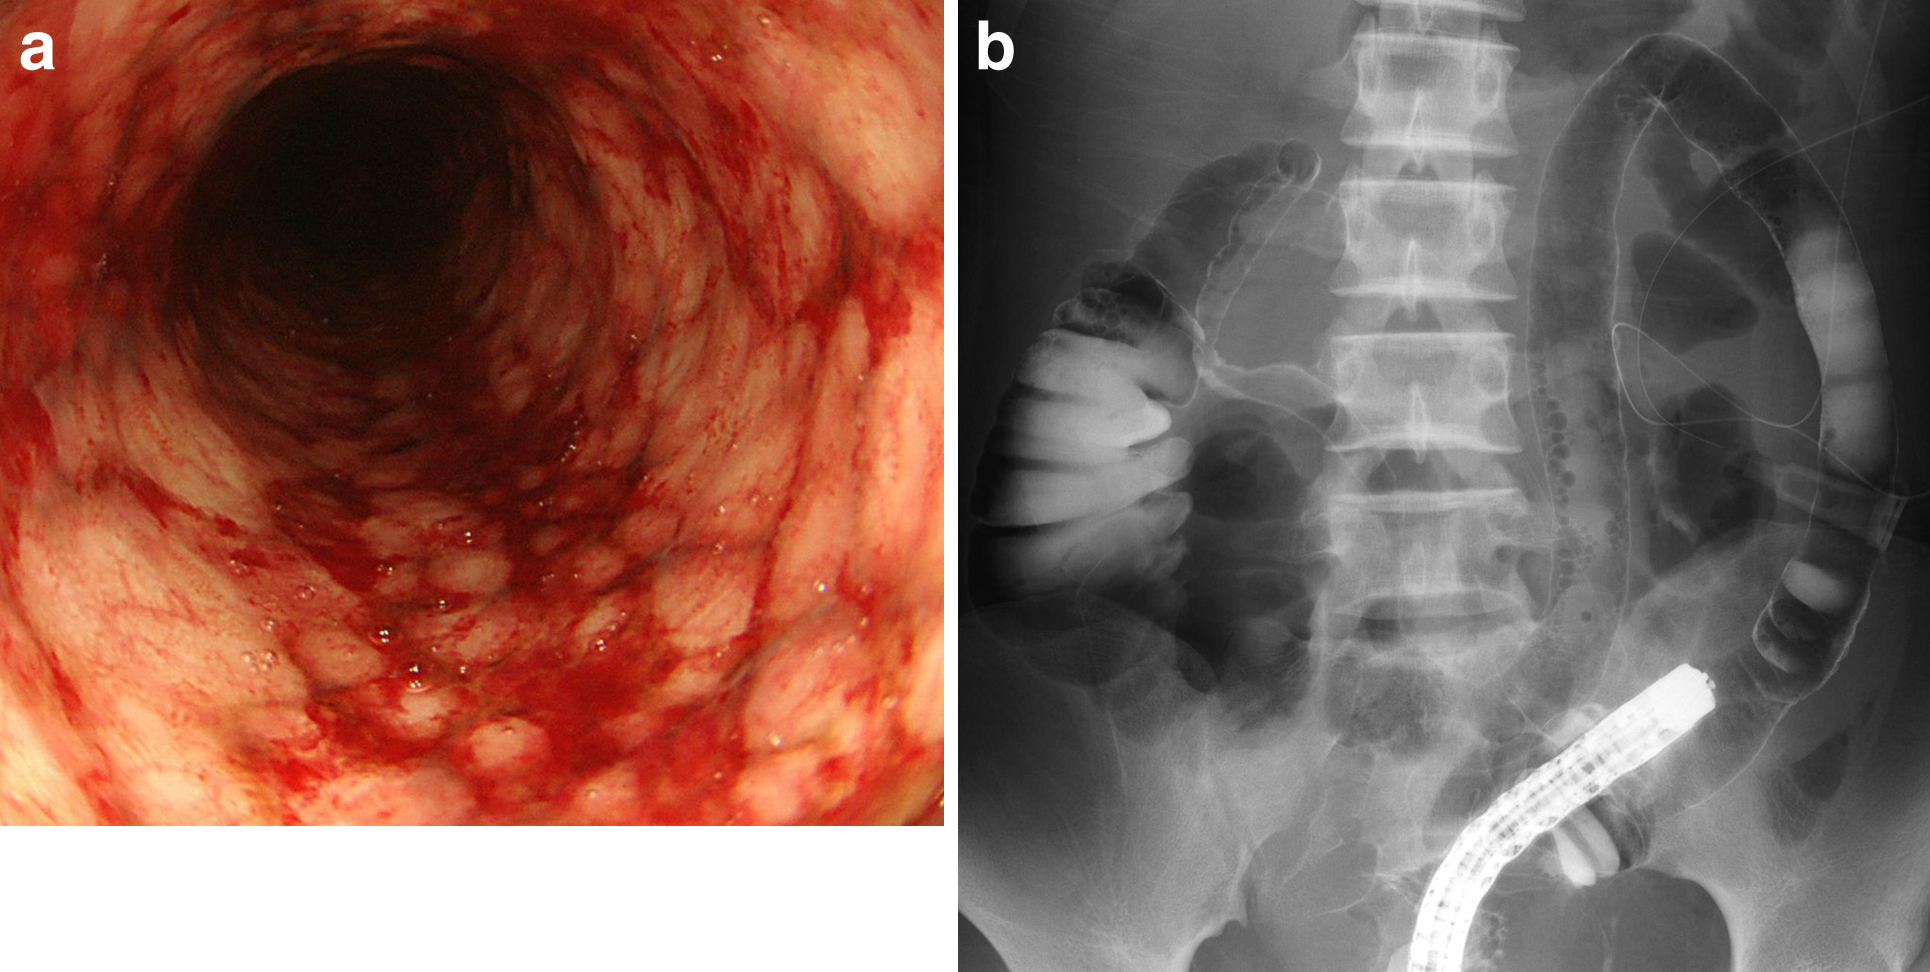

下部消化管内視鏡検査所見:直腸に便塊が貯留していたが,水洗,吸引しながらS状結腸の拡張腸管まで到達した.S状結腸以深の結腸粘膜は紫~黒色に変化していた(Fig. 3).

Colonoscopy showed the mucosa of the sigmoid colon turning purplish or blackish.

術後経過:術後は敗血症性ショックとなり,カテコラミン投与や人工呼吸管理などの集中治療を要したが,第4病日に気管内チューブを抜管,第5病日に集中治療室を退室した.第25病日に透視下下部消化管内視鏡検査を行った.横行結腸にびまん性の炎症性変化が残存しており,易出血,全周性の粘膜脱落を認めた(Fig. 5a).右側横行結腸は狭窄が強く,内視鏡は通過できなかった.アミドトリゾ酸ナトリウムメグルミン液にて造影を行ったところ,右側横行結腸に高度の狭窄,左側横行結腸から下行結腸にかけて鉛管状の変化を認めた(Fig. 5b).この時点での回腸人工肛門の閉鎖は不可能と判断,時間経過による改善に期待し,第35病日に退院した.第85病日,再度透視下下部消化管内視鏡検査を行った.右側横行結腸は前回と同様に狭窄が強く,内視鏡は通過できなかった.左側横行結腸から下行結腸までは軽度の狭窄と点状出血を認めた(Fig. 6a).アミドトリゾ酸ナトリウムメグルミン液による造影では,右側横行結腸の著明な狭窄,左側横行結腸から下行結腸までの軽度の狭窄,鉛管状変化を認めた(Fig. 6b).自然経過による改善は困難と判断し,第103病日に結腸亜全摘術を施行した.

a. Colonoscopy on day 25 showed diffuse inflammation which involves hemorrhagic changes and mucosal deciduation in the entire circumference of the transverse colon. b. Meglumine sodium amidotrizoate enema on day 25 showed severe stenosis at the right side of the transverse colon, through which the scope could not pass. The lead-pipe appearance from the left side of the transverse colon to the descending colon was seen.

a. Colonoscopy on day 85 showed the mucosal petechial hemorrhage from the left side of the transverse colon to the descending colon. b. Meglumine sodium amidotrizoate enema on day 85 still showed severe stenosis at the right side of the transverse colon, through which the scope could not pass. Mild stenosis and the lead-pipe appearance from the left side of the transverse colon to the descending colon remained.